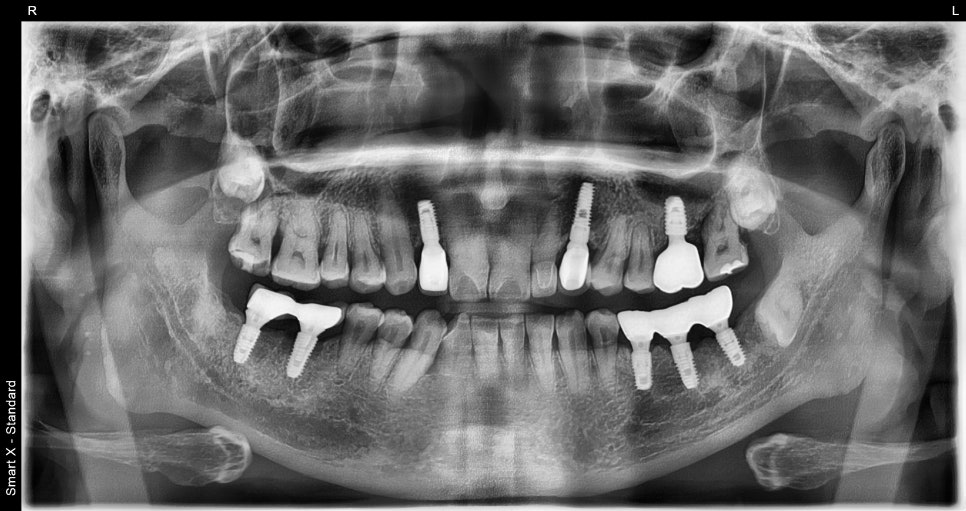

초진 내원당시

이번 케이스는 68세 남성 환자로, 잇몸이 심하게

붓고 통증이 발생한 상태에서 내원하셨습니다.

기존에 약을 복용하셨지만 증상이 호전되지 않았고,

어금니 부위의 통증이 점점 심해지는 상태였습니다.

검사 결과 어금니 주변 잇몸 내부에 고름이 형성된

치주농양 상태였으며, 뿌리 주변 뼈가 손상된 상태가

확인되었습니다.